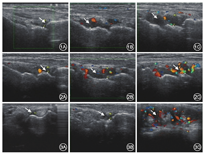

采用意大利百胜公司MyLab30彩色超声成像系统,10~18 MHz高频线阵探头,收集所有患者双腕、双手第1~5掌指关节、第1指间关节,第2~5近端指间关节关节腔积液、滑膜增生、滑膜炎、骨侵蚀、肌腱炎等的情况。判断标准参照RA和结缔组织病预后评估组织工作组制定的标准[1]。(1)关节腔积液:测量双腕关节腔内低回声区垂直距离的最大值;(2)滑膜增生的灰度等级(GS):0分为无滑膜增生,1分为轻度滑膜增生,2分为中度滑膜增生,3分为重度滑膜增生;(3)滑膜炎:应用彩色多普勒检测滑膜内血流能量多普勒(PD)信号强弱并进行半定量评分:0分为无滑膜血流信号,1分为单一或孤立的血流信号,2分为交汇的血流信号,但不超过滑膜面积的1/2,3分为血流信号超过滑膜面积的1/2;(4)骨侵蚀:采用2进制,无骨侵蚀为0,有骨侵蚀为1;(5)肌腱炎:无肌腱炎为0分,有肌腱炎为1分,并记录双腕关节从尺侧到桡侧肌腱炎的部位。超声评估总分通过分别计算双腕、双手第1~5掌指关节、第1指间关节,第2~5近端指间关节关节腔积液、滑膜增生、滑膜炎、骨侵蚀及肌腱炎总和得出(图1,图2,图3)。